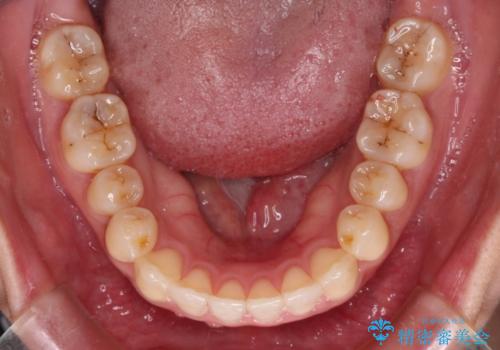

すきっ歯とオープンバイトをインビザラインで改善

- 前歯の上下スペースと前歯の隙間を気にして来院された患者様です。

インビザラインにより上下の前歯の隙間を閉じていくこととしました。

上下の隙間に舌が入り込むことが、すきっ歯やオープンバイトの原因であったため、舌の筋肉のトレーニングも並行して行い、後戻りの抑制を図りました。